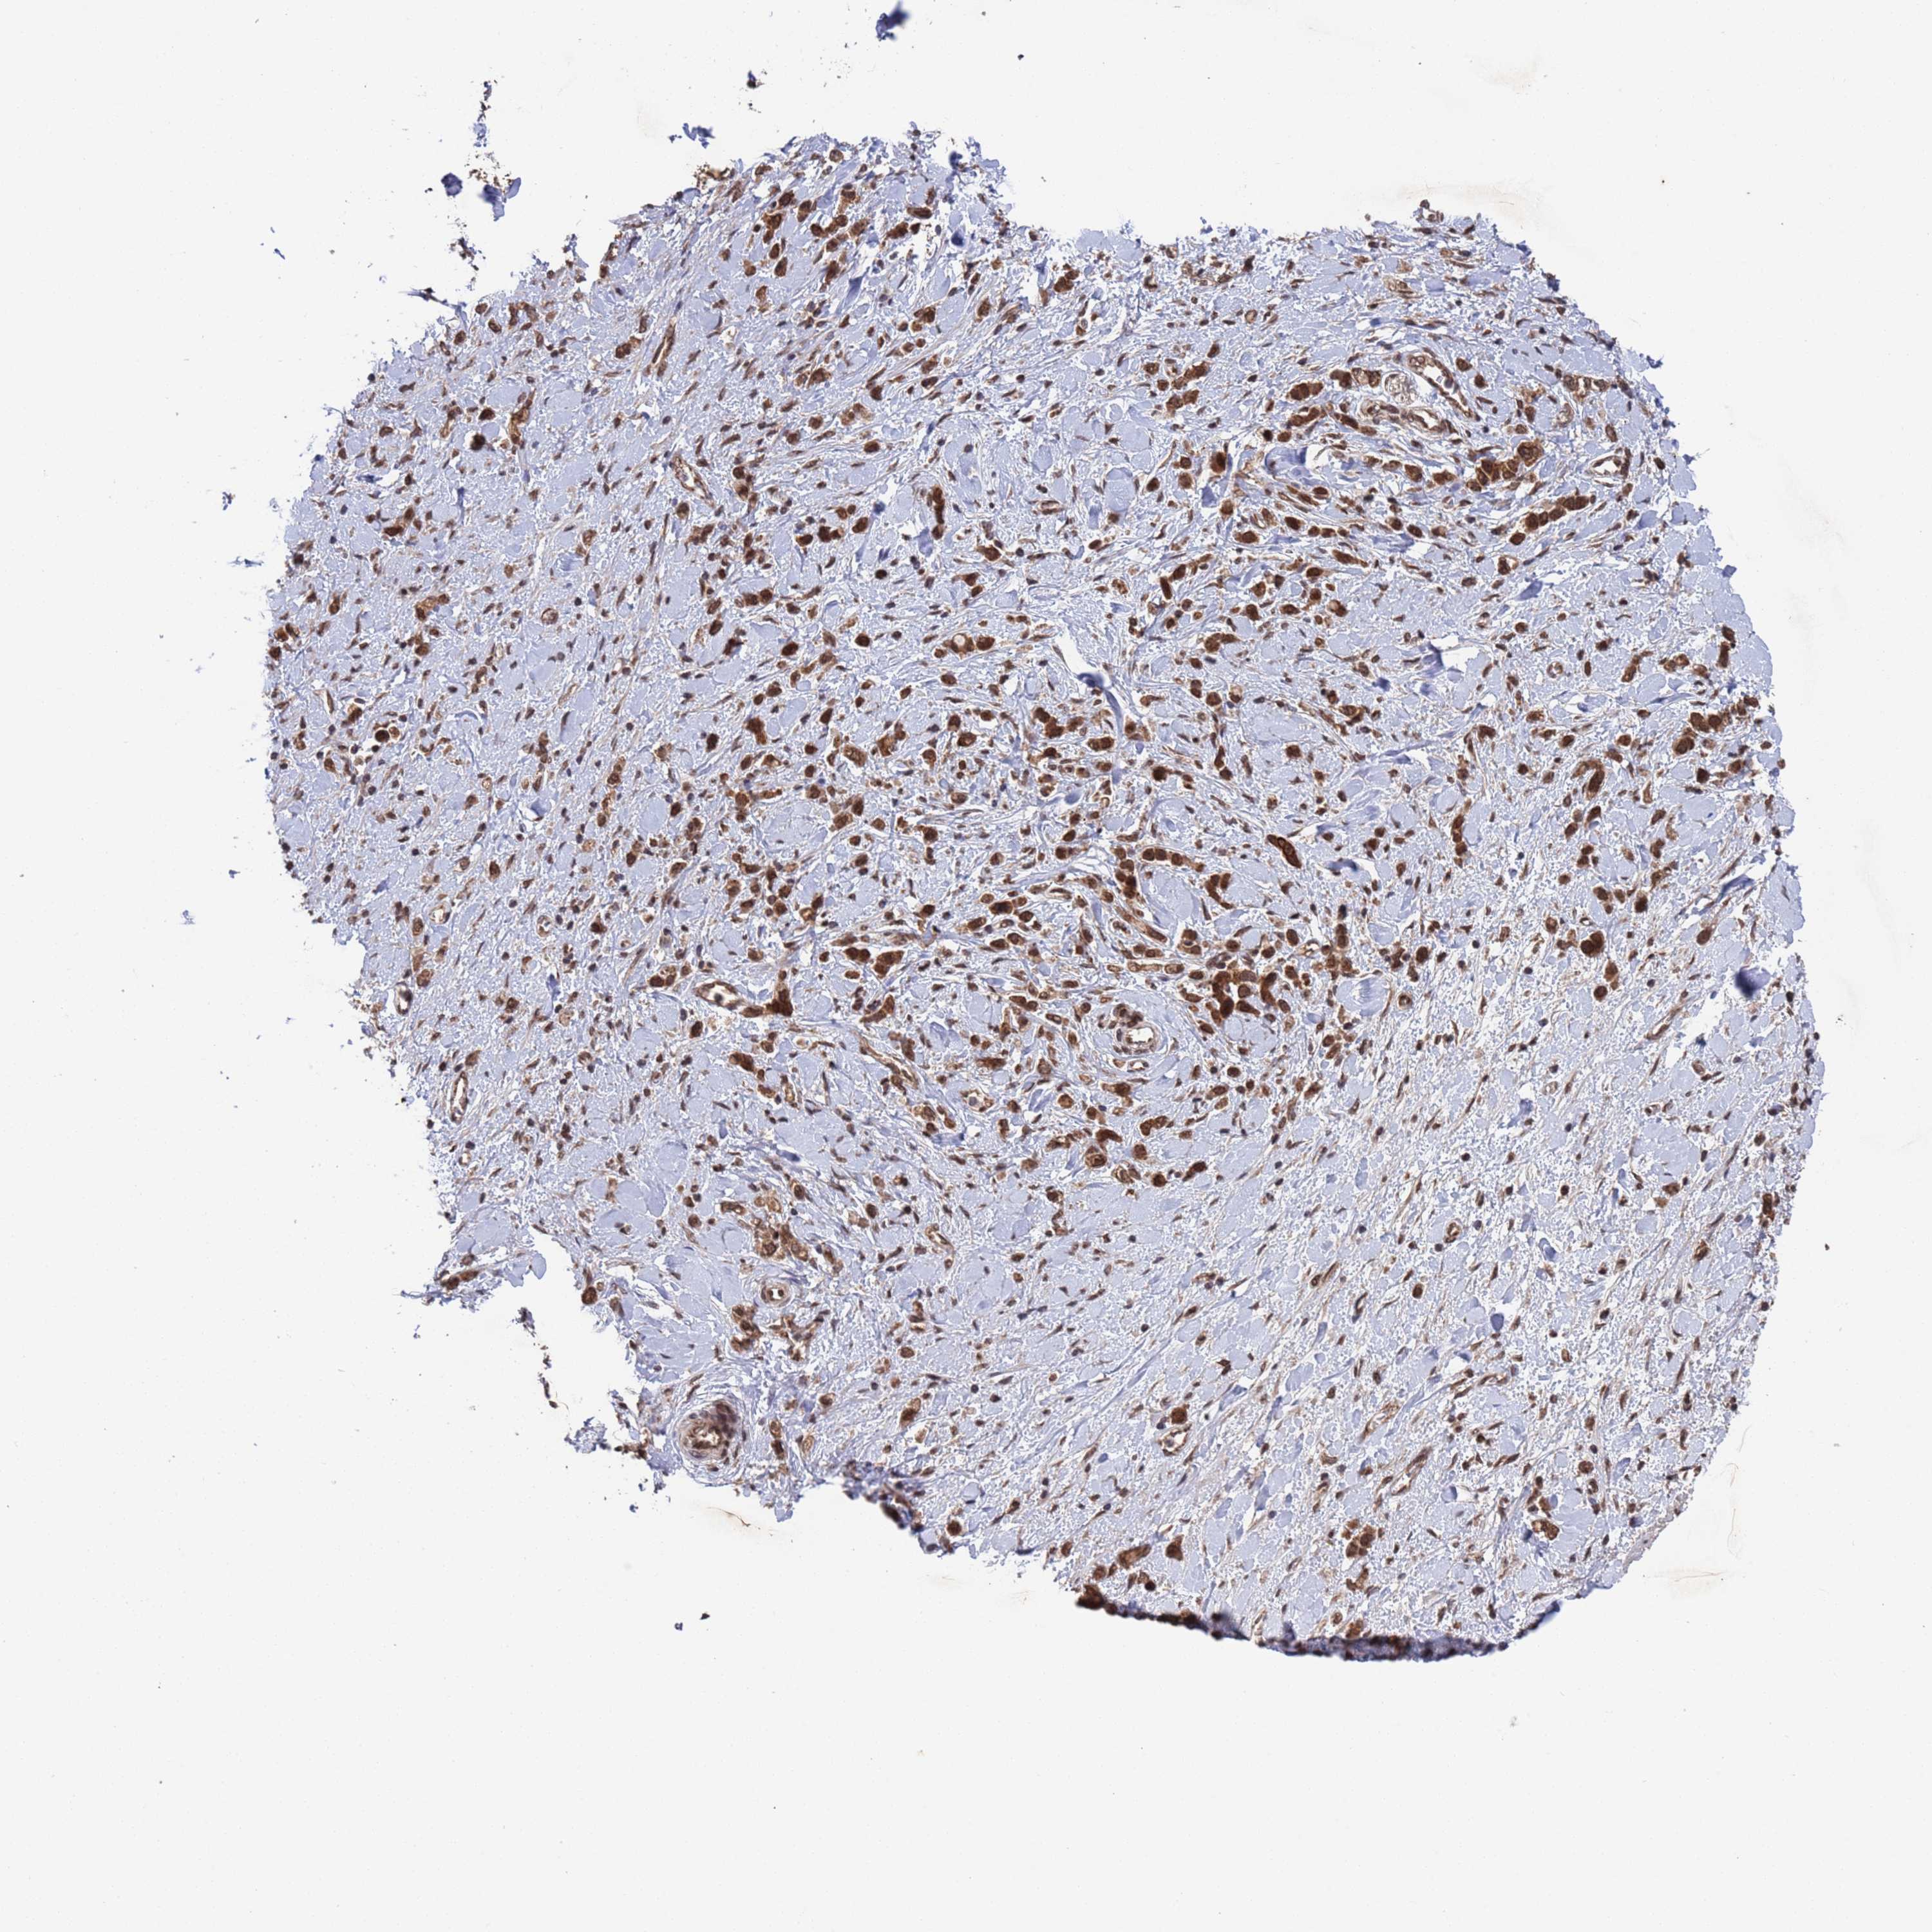

STOMACH CANCER - Protein expressioni

A mouse-over function shows sample information and annotation data. Click on an image to view it in a full screen mode. Samples can be filtered based on level of antibody staining by selecting one or several of the following categories: high, medium, low and not detected. The assay and annotation is described here.

Antibody stainingi

Antibody staining in the annotated cell types in the current human tissue is reported as not detected, low, medium, or high, based on conventional immunohistochemistry profiling in selected tissues. This score is based on the combination of the staining intensity and fraction of stained cells.

Each image is clickable and will lead to virtual microscopy that enables deeper exploration of all samples and also displays staining intensity scores, fraction scores and subcellular localization as well as patient and tissue information for each sample.

Antibody HPA047658

Antibody HPA058392

Staining

High

Medium

Low

Not detected

Intensity

Strong

Moderate

Weak

Negative

Quantity

>75%

75%-25%

<25%

None

Location

Nuclear

Cytoplasmic/membranous

Cytoplasmic/membranous,nuclear

Adenocarcinoma, NOS

Adenocarcinoma, High grade